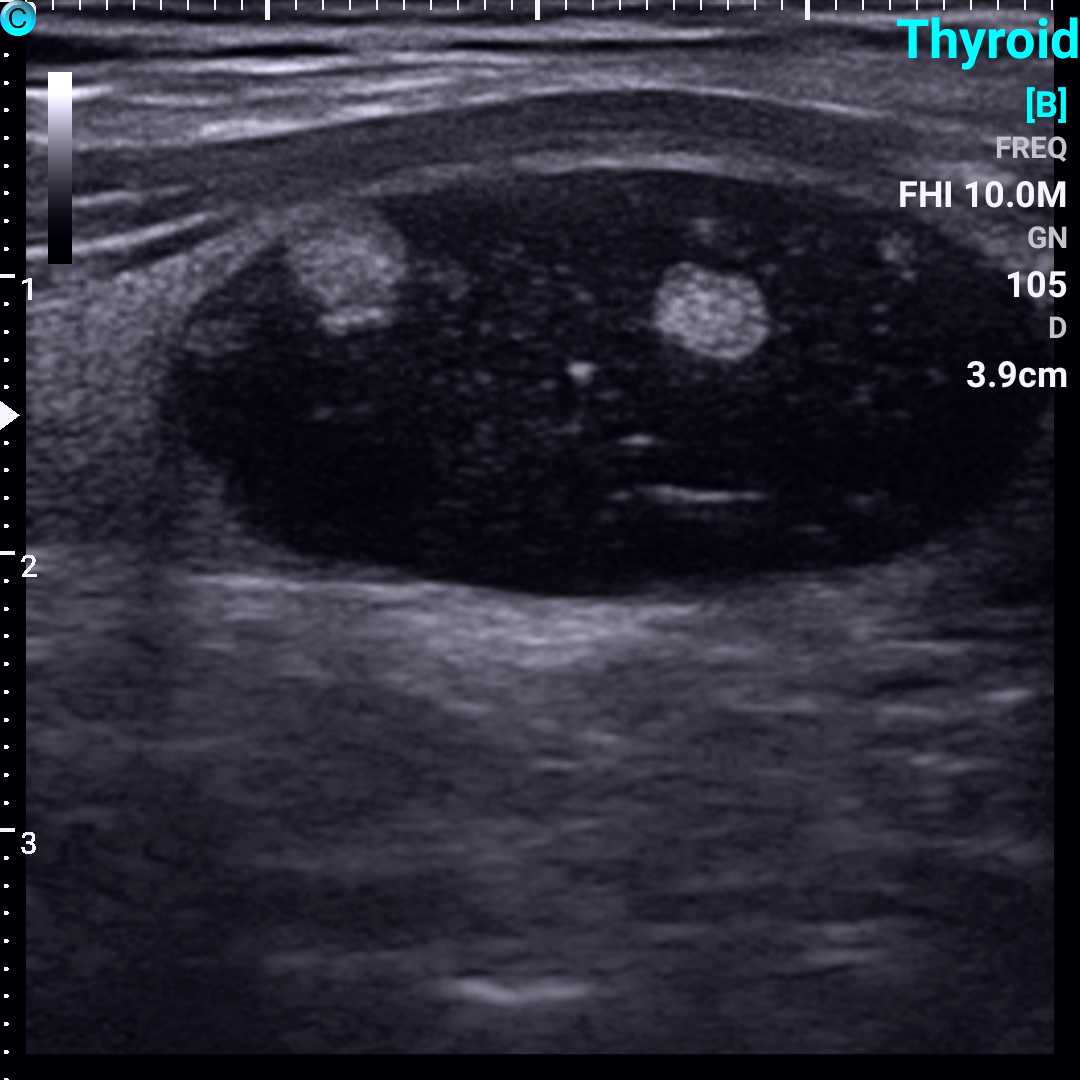

甲状腺囊性,囊实性和实性结节超声图像